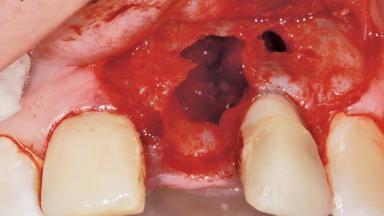

Late Placement of an Implant in a Maxillary Left Central Incisor Site

A 36-year-old female patient was referred for the replacement of the upper left central incisor (tooth 21), which had fractured. Although the tooth had been asymptomatic for many years, the crown began to loosen, at which time she presented to her dentist for an assessment. Teeth 21 and 22 had both been endodontically treated many years previously. She was a healthy individual and a non-smoker.

The crown of tooth 21 was splinted to the adjacent teeth with composite resin, and the gingiva was inflamed.

| Bone Volume | Deficient horizontally, requiring prior grafting |